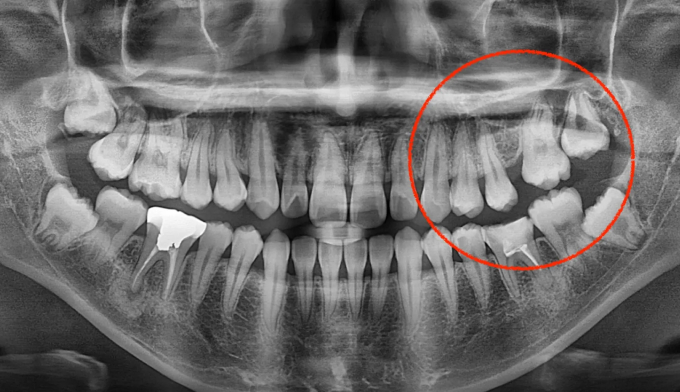

어금니가 선천적으로 없는 경우, 어금니 사이에 공간이 유지된 채 악골의 성장이 완료됩니다. 벌어진 어금니 공간은 음식물이 잘 끼게 되므로, 충치가 생길 수 있는 가능성이 높아지고 냄새가 나기도 합니다.

이때, 이러한 공간을 벌려서 임플란트를 식립하는 방법이 우선적으로 고려됩니다. 하지만 후방에 사랑니가 위치한 경우, 임플란트 대신 사랑니를 당겨서 쓰게 되면 내 치아를 살리면서 동시에 임플란트라는 인공 구조물을 식립하지 않아도 되기 때문에 교정치료가 훨씬 효율적인 치료가 됩니다.

교정기간은 8개얼 소요되었고, 안적적으로 유지하기 위해 일정기간동안의 유지장치 착용이 필수입니다.